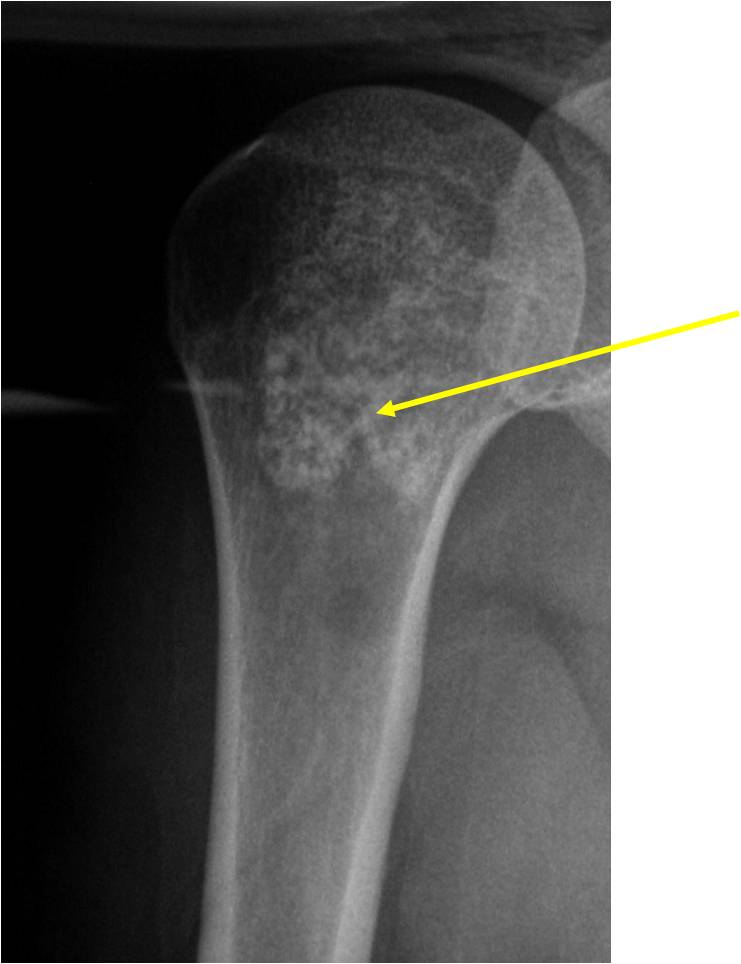

- Proximal Humerus, Femur most common long bones

- Localized, radiolucent defect usually with punctate calcifications

- Calcifications are typical but not always present

- Matrix may demonstrate various degrees of calcification

- Calcifications are stippled, punctate, popcorn like calcifications and “Ring and Arc” calcifications

- Cartilage tumors grow in a lobular manner. The perimeters of the lobules undergo

- enchondral ossification that may calcify. If the entire perimeter of the lobule calcifies it appears

- radiographically as a “Ring”. If a portion of the perimeter of a lobule calcifies it forms an “Arc” on

- an X-ray.

Plain X-Ray:

- Geographic lytic lesion

- Central often metaphyseal in long bones

- Expansile remodeling with thinned cortex

- Chondroid matrix with calcifications in majority of tumors

- Approximately 20% have limited or no calcifications

- There should never be any cortical destruction nor a soft tissue component. If this exists then the tumor must be a chondrosarcoma.

- Endosteal scalloping and cortical expansion is acceptable for phalangeal tumors. In most benign long bone cartilage tumors there is minimal endosteal scalloping but there should be no cortical expansion nor thickening. There should be no cortical destruction and no soft tissue component associated with an enchondroma. Cortical destruction, periosteal thickening, cortical expansion and a soft tissue component indicates a chondrosarcoma of the long bone.